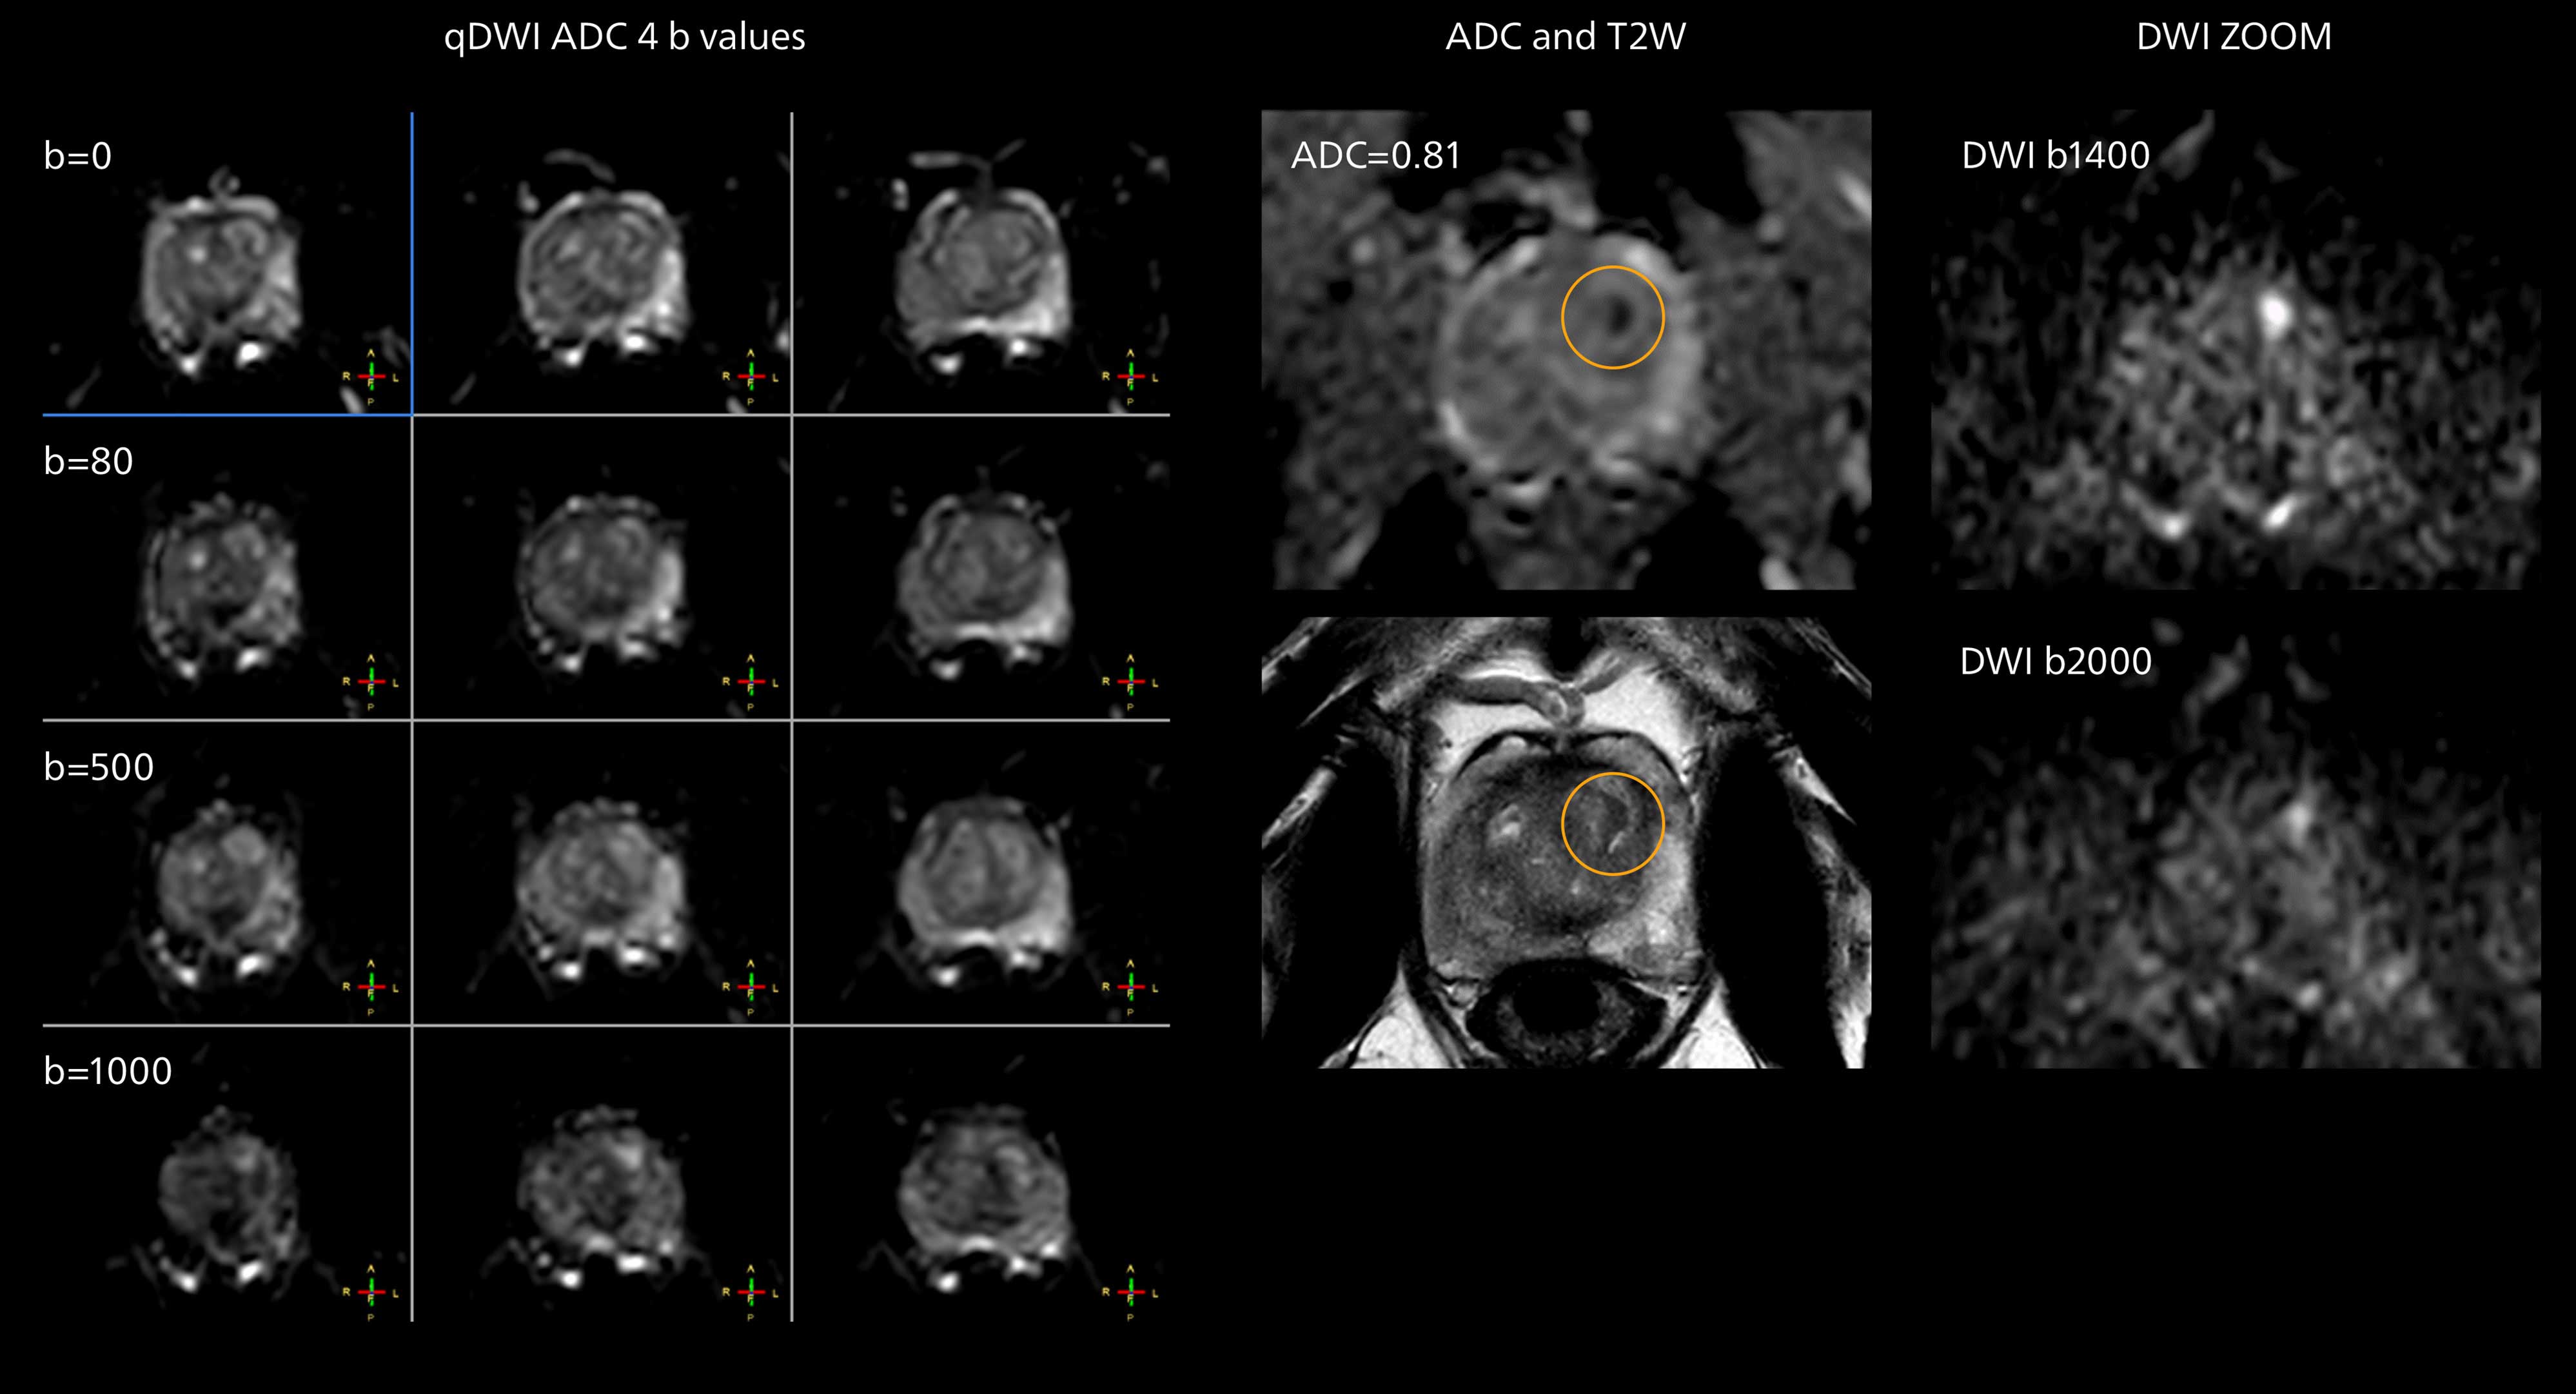

Imaging of the optic nerve sheath

High-resolution MRI impressively demonstrates the compression and narrowing of the right optic nerve in this case of optic nerve sheath meningioma (ONSM). The coronal T2-weighted images show the hyper-intense, half-moon shaped lesion, that is clearly visible in the axial T1W image after contrast injection (right). These imaging findings were so convincing that there sponsible neurosurgeon did not consider a pretherapeutic histological clarification.

High resolution-MRI impressively demonstrates the compression and narrowing of the right optic nerve in this case of optic nerve sheath meningioma (ONSM). The coronal T2-weighted images show the hyper-intense, half-moon shaped lesion, that is clearly visible in the axial T1W image after contrast injection (right). These imaging findings were so convincing that there sponsible neurosurgeon did not consider a pretherapeutic histological clarification.